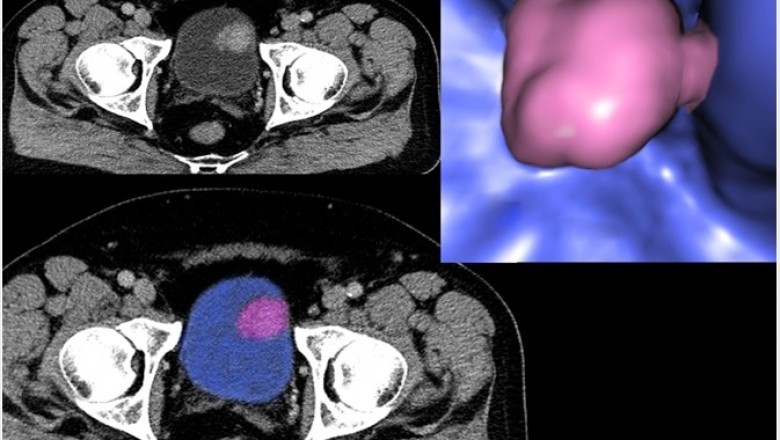

There are many different types of Non-Invasive Cancer Diagnostics available. These tests include the use of a PAP or nasal passage plethoracic device, mammography, magnetic resonance imaging, or CTV. Each one has its own purpose and some of them may be combined to improve accuracy. Non-Invasive Cancer Diagnostics are witnessing wider adoption across the globe. With non-invasive diagnostics, it is possible to examine tissue in its natural state, which allows continued monitoring of the skin site.

Single-photon emission computed tomography is also more accurate in detecting small abnormalities. The sensitivity of this method can be adjusted easily with the help of fluoroscopy. Immunohistochemistry detects abnormalities by the immune system's response to biological agents. It is one of the most widely used cancer detection techniques. The most common methods are enzyme-linked immunosorbent assay (ELISA, EIA), immunohistochemistry with enzyme-linked restriction enzymes (hrG flanked, rhrG), and soluble markers (sera). Other techniques include bead-based immunohistochemistry with proteins and lectins and virus-based antigens. Recently, in May 2021, Tzar Labs and Epigeneres Biotechnology developed RNA-marker-based cancer detection technology rooted in stem cell biology.